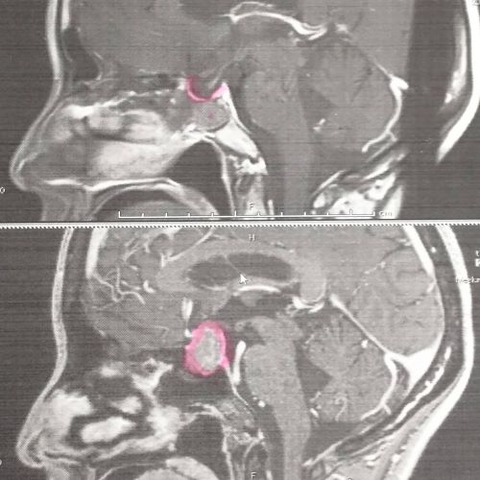

下が術前で、上が現在。

分かりやすい!

でっかいのがキレイに無くなっています。